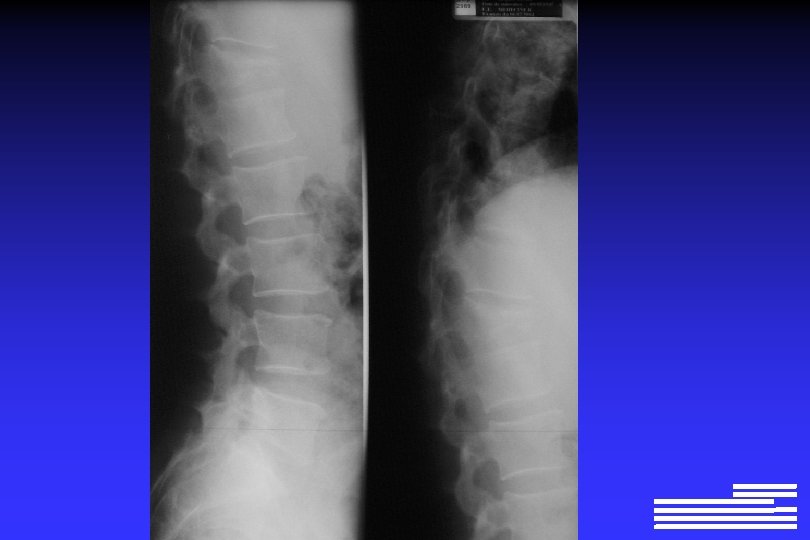

Explorations à effectuer pour le diagnostic positif et différentiel l Radiographie du squelette complet Ø Lésions lytiques à l’emporte-pièce Ø Lésions « ostéoporose diffuse » Ø Lésions condensantes (rares +++ !, 0, 5 à 3% des cas)